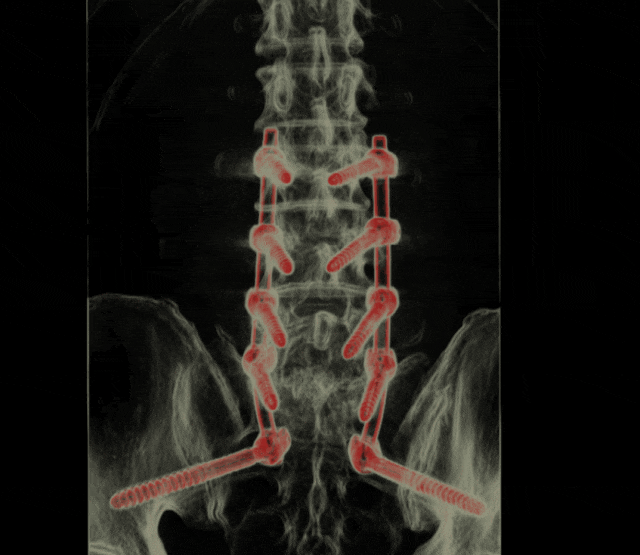

对于脊柱感染等复杂病例,3D 外视镜结合S2 AI螺钉技术。从感染控制、手术方案设计到术后康复,每一个环节都反复推敲。团队结合患者的病因差异(原发与继发)、身体状况,分别制定了个性化治疗计划,既要彻底清除感染病灶,又要最大程度保护脊柱脊髓功能,清除病灶同时重建脊柱稳定性,让患者即刻摆脱疼痛,迅速恢复正常生活。

术后复查